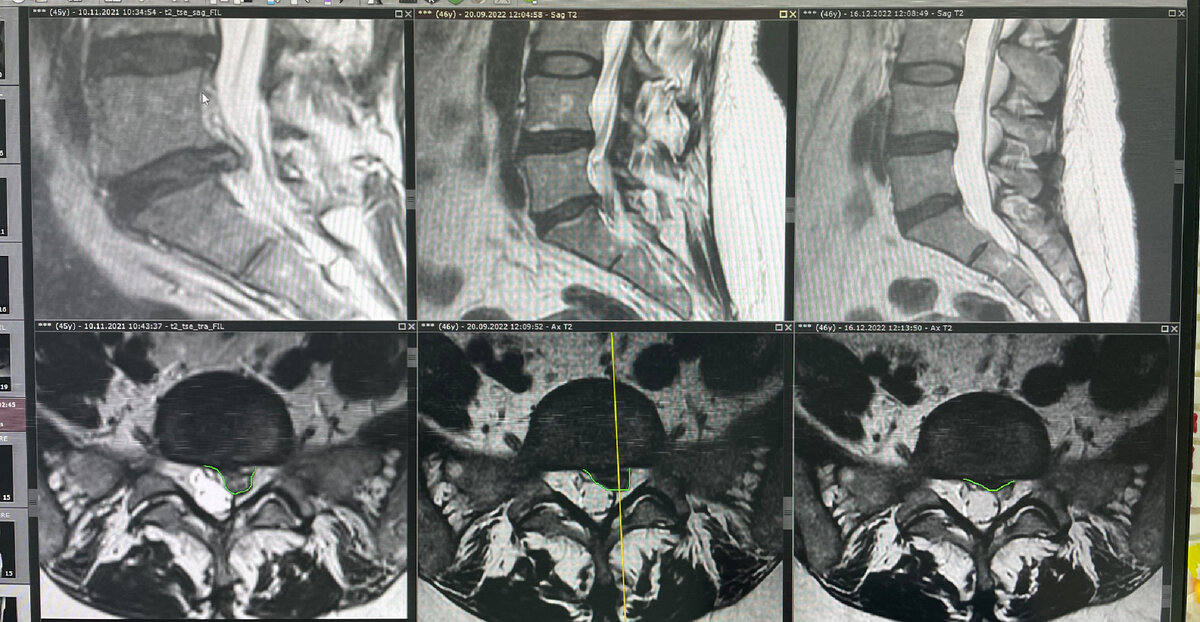

Результат лечения грыжи диска L4-L5. Общее время консервативной терапии 3 месяца